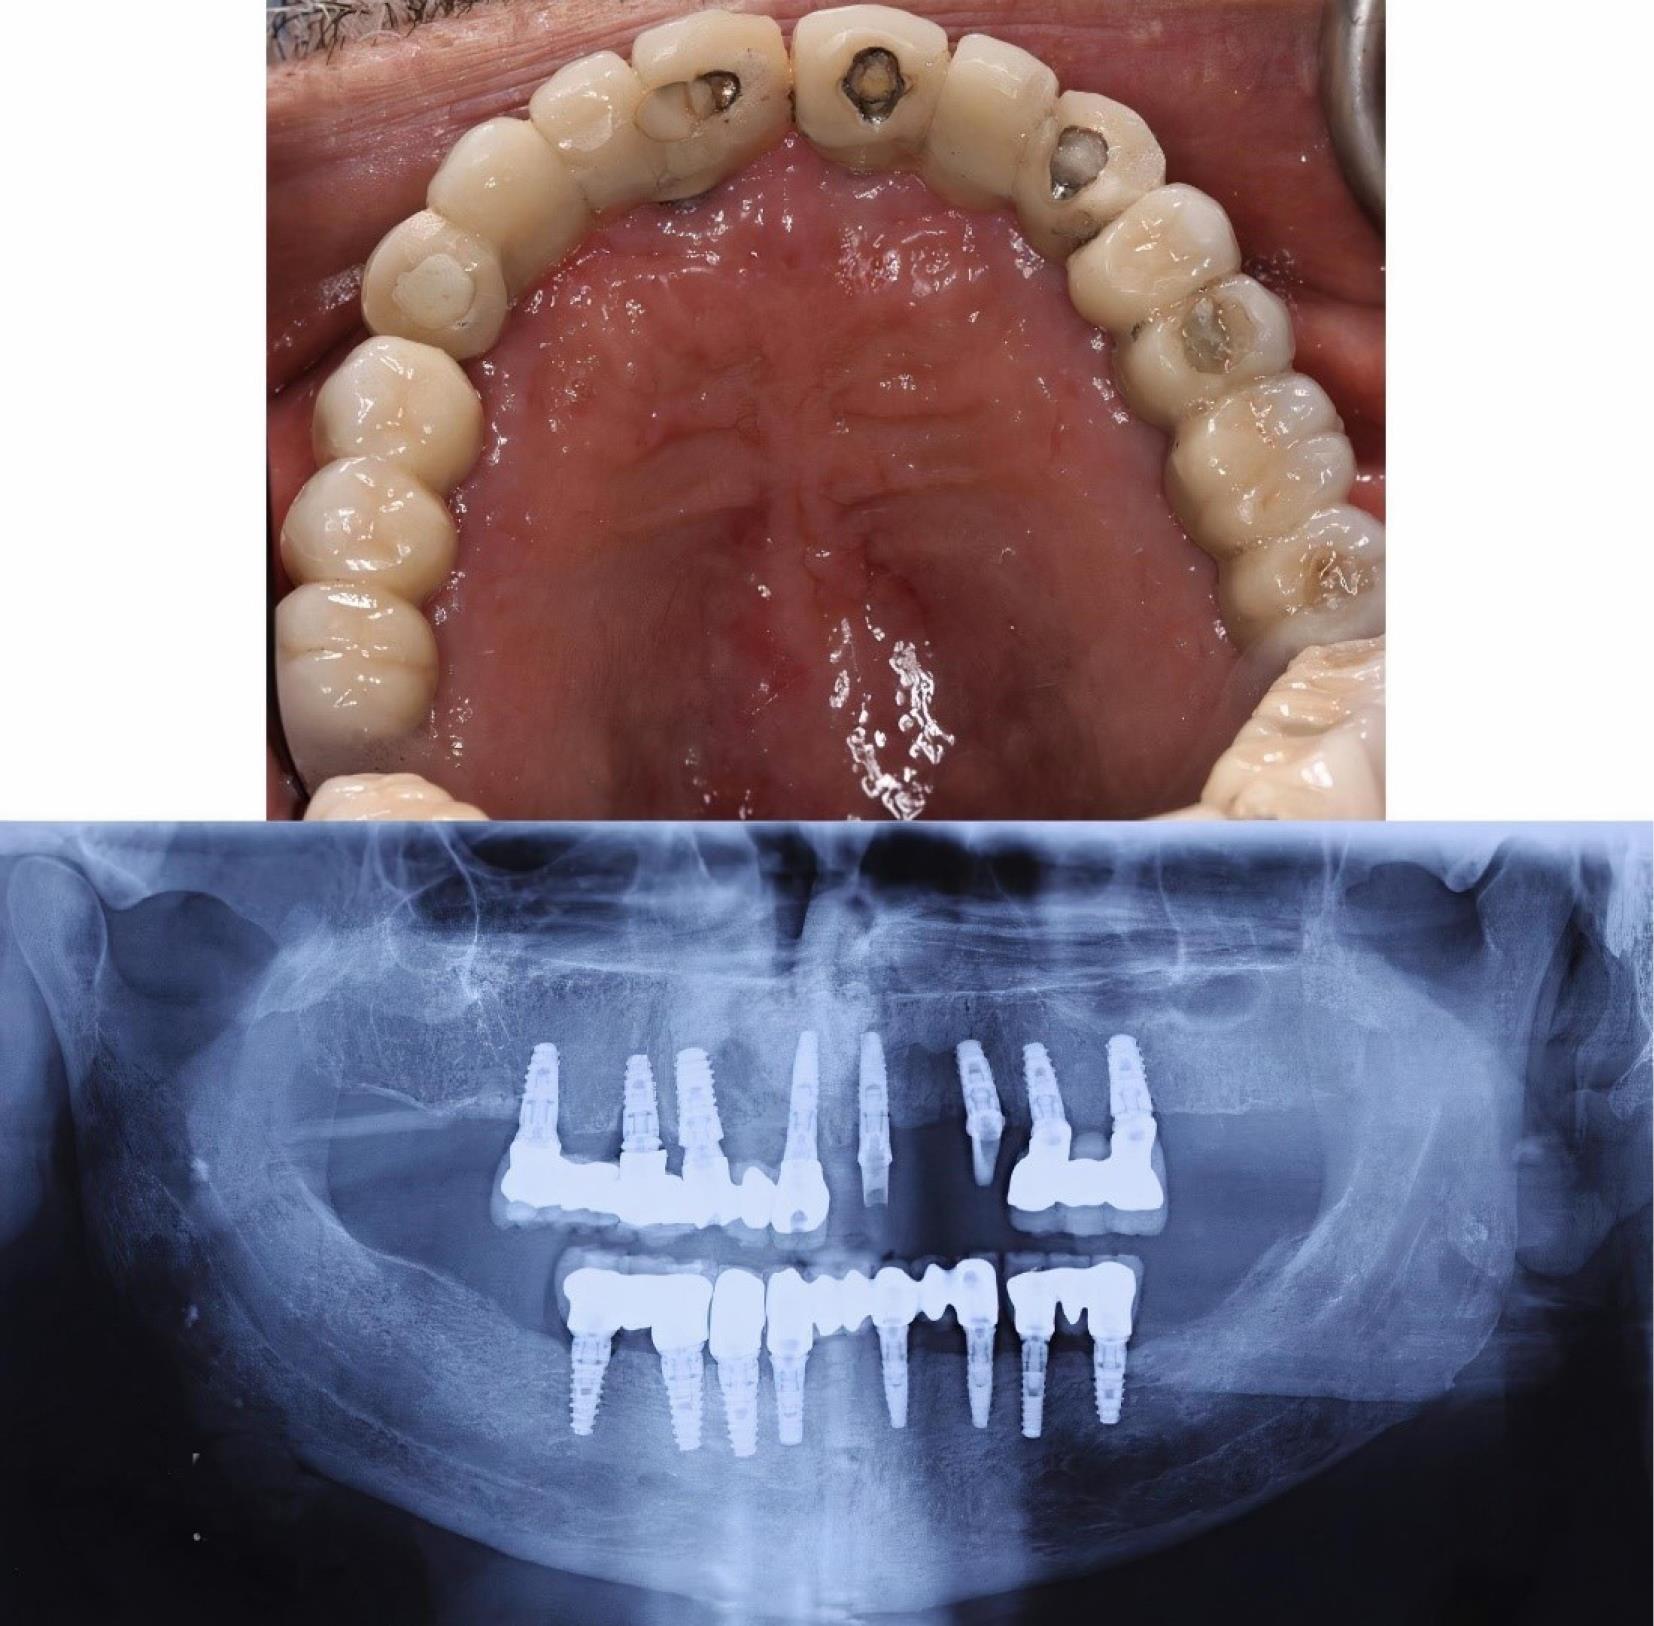

Histopathological findings

Histological evaluations revealed a cystic lesion lined with variable cuboidal, stratified squamous epithelium and focally ciliated columnar epithelium. The cyst wall consisted of fibrovascular tissue, inflammatory cell infiltration, hemorrhage, sections of adipose tissue, and normal bone trabeculae (Figure 4).

Figure 4.

Histologic images of the sample ( × 40). A: The black arrow shows adipose tissue. B: The black rectangle shows the lining cells of the cyst